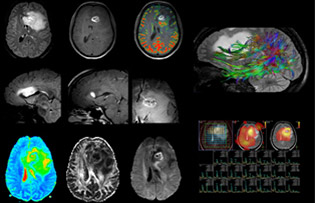

Comprehensive exam answers complex brain tumor questions

Dr. Savatovsky uses five or six different ExamCards for imaging a mass or a known tumor in the brain. “If there is a mass in the brain we try to characterize it to inform the neurologist for determining next steps or to help neurosurgeon prepare for a surgery or biopsy. For follow-up after treatment we have different protocols for different treatments and we adapt for intra- or extra-axial tumors.” “That is the most comprehensive exam we would do. Ingenia has the good spatial resolution and high SNR to provide all this information, and the flexibility to use shorter sequences, so we can do a very comprehensive examination in a limited time.”

“The biggest challenges are properly characterizing the lesion and giving the surgeon all the information needed, such as the location of vessels and functional areas. Sometimes a very comprehensive exam is necessary, such as when a mass has been discovered at another hospital after which the patient is referred to us. We then do both lesion characterization and preoperative imaging in one exam, so both morphologic and functional assessment. For morphologic assessment we will use pre- and post-contrast T1-weighted imaging, FLAIR to assess infiltration, and diffusion. For functional characterization we will perform perfusion, spectroscopy, and susceptibility weighted imaging to look for micro vessels or micro hemorrhage inside the lesion[4]. For preoperative imaging we perform specific morphologic imaging that is compatible with the navigation system; depending on the location of the tumor, we would do fMRI or DTI.”